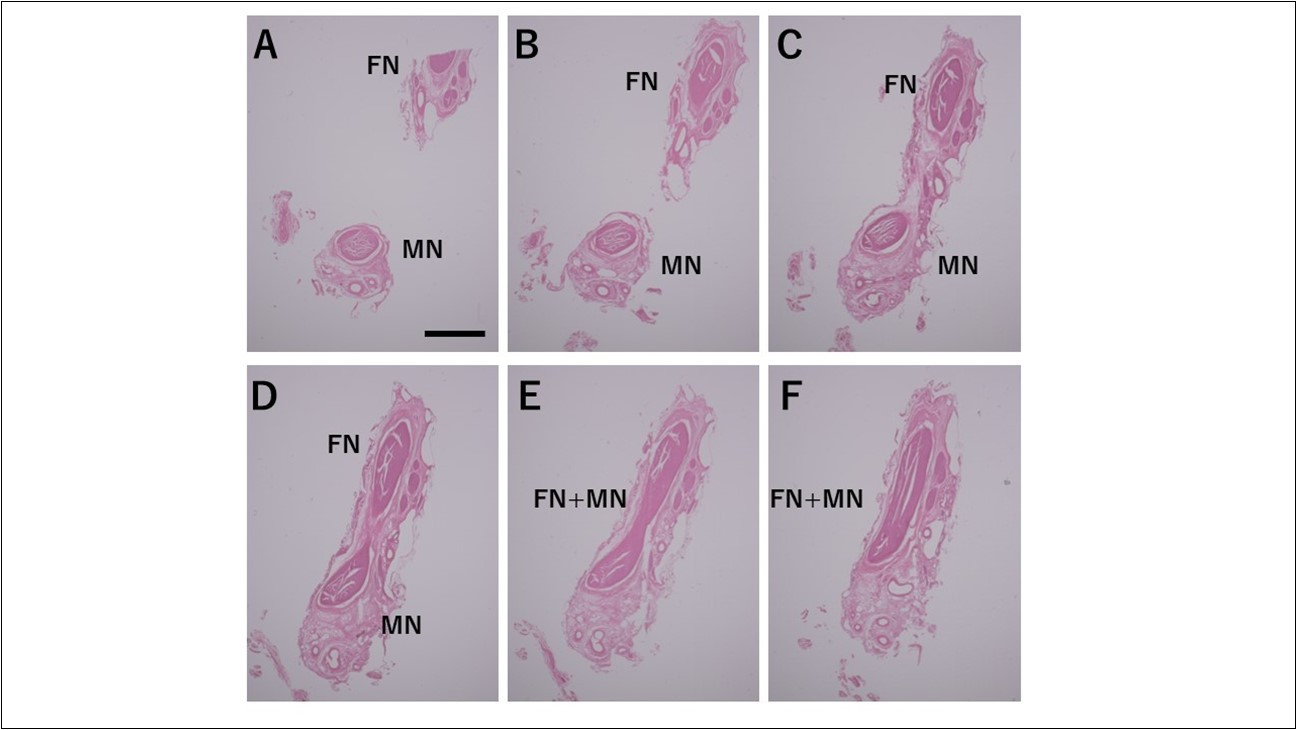

Histological Observations Using the Serial Sections

From the medial side of the facial nerve, we made thin slices that terminated at the anterior loop. These were used to make histological observations of the communicating branches of the facial nerve and mental nerve. At first, we observed the marginal mandibular branch along with blood vessels and connective tissue. There were several nerves, and there were repeated ruptures, fusions, confluences, and separations at the perineurium level, particularly at the epineurium. Once the inferior alveolar nerve appeared in the section (Figure 4A), we first observed that it was connected at the epineurium (Figure 4C). Next, we observed that the nerve fibers formed a confluence immediately following connection with the perineurium (Figure 4D, E). Following this confluence, there was a complete fusion within the perineurium, as it was impossible to differentiate between the two with hematoxylin and eosin staining. I observed similar findings in all specimens.

Figure 4.Fusion between the inferior alveolar nerve and the marginal mandibular branch of the facial nerve as observed microscopically Bar = 200um

The Origin of the Nerves that Compose the CommuniCating Branches and the Types of Nerve Fibers

Based on the results obtained in this study, the mental nerve and the marginal mandibular branch of the facial nerve are completely fused at the perineurium. Most nerve diagrams indicate that the mental nerve is only a sensory nerve, and that the marginal mandibular branch of the facial nerve is a pure motor nerve. However, we found that there is a need for autonomic nerves to be present in the lower face region, where there are salivary glands and sweat glands, including the lower lip and chin (the regions of these nerves). Hence, we aimed to determine where these nerves originate. In the present study, we observed that the vasomotor nerve of the facial artery branched off from the buccal branch and the marginal mandibular branch of the facial nerve (Figure 2※), and we identified the fact that there are sympathetic and parasympathetic fibers in the facial nerve. This was also confirmed micro-anatomically. Figure 5 shows a cross-section of the optic nerve, and Figure 6 shows a cross-section of the mental foramen region of the mandibular nerve. Tyrosine hydroxylase immunostaining stained the sympathetic nerves (provided by lecturer Masahito Yamamoto of the Department of Anatomy, Tokyo Dental College). The trigeminal nerve includes sympathetic fibers, and when the two sections are compared, the optic nerve has a substantial number of such fibers, whereas the mandibular nerve has very few. Matsubayashi 10 wrote extensively on this issue. It is known that the trigeminal nerve, which is the great auricular nerve, auriculotemporal nerve, and zygomatic branch of the facial nerve, consists of cutaneous nerves of the face and sympathetic nerve fibers, although there are few sympathetic nerve fibers in the maxillary nerve or mandibular nerve.

The communicating branches of the mental nerve and marginal mandibular branch of the facial nerve are normal anatomical structures that are fused at the perineurium level. These structures may supply autonomic nerves to the mental nerve region from the facial nerve, although further studies are needed to explore and understand this structure and its functions in-depth.